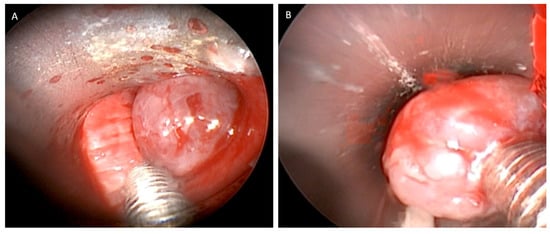

After intubation, the removal of the mucoid impaction showed an endobronchial tumor originating from the airway wall of the right or left main bronchus, the rigid bronchoscope can be placed in the obstructed main bronchus, ensuring good ventilation management and avoiding blood accumulation in the contralateral bronchus. The lesions were polypoid in appearance, rounded, pinkish in color, and well vascularized, with a hard-elastic consistency [10].

They were positioned at the entrance to the right or left main bronchus just below the carina, so as to completely obstruct the airway lumen (Figure 1). Rigid and flexible bronchoscopes were used to obtain the maximum amount of tissue for correct histological diagnosis.

Figure 1. Well-vascularised polypoid lesion of 9 mm in diameter, rounded, pink in colour, with a hard elastic consistency (A,B) detected at the beginning of the right main bronchus (C).